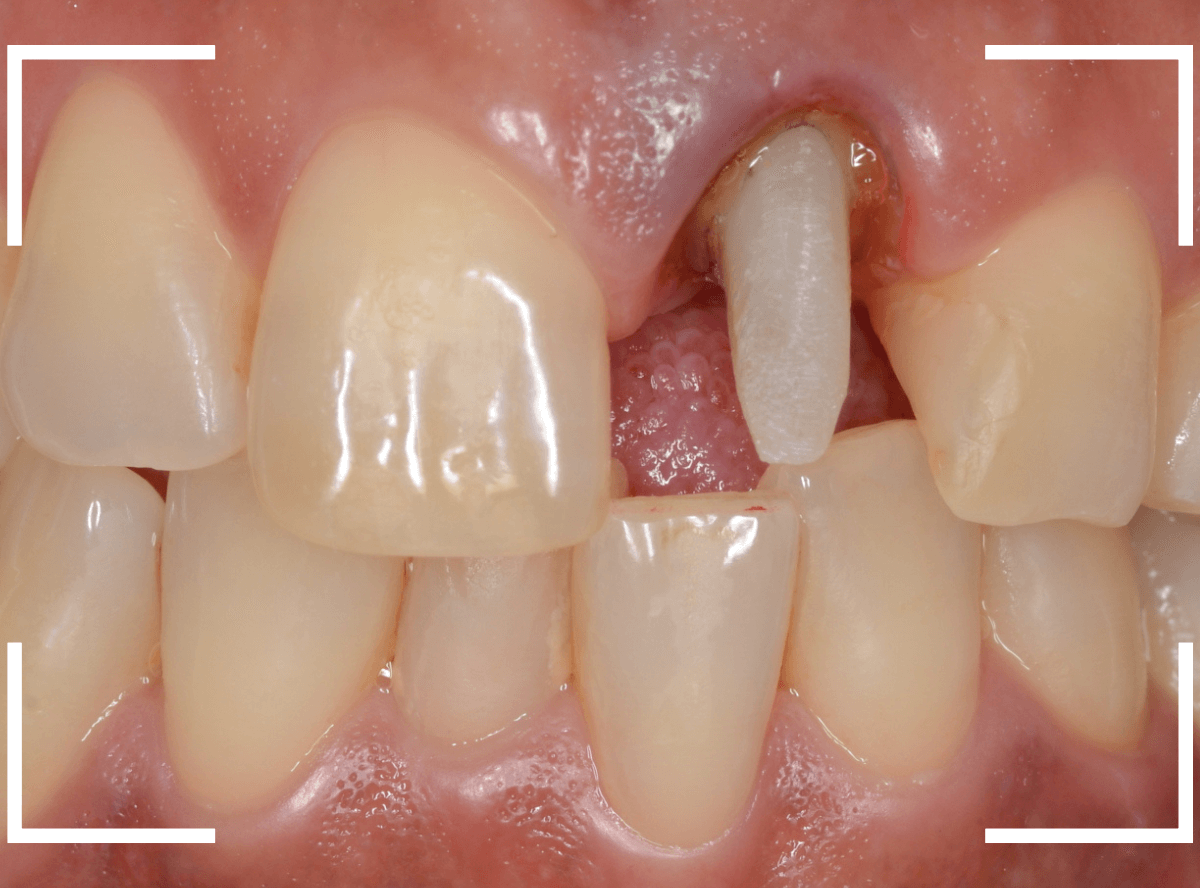

さし歯を被せるために、歯の土台をたてて、歯を削ります。

歯の高さが低く、このままさし歯を作っても、すぐに取れてしまう事が予想されます。

隣りの歯と比べても歯肉の際が浅いため、若干歯肉を切開して、歯の高さを稼ぎます。

歯肉を切開した部分に、仮歯のレジンを盛って確認します。

大体、隣の歯の高さと合わせる事が出来ました。

しばらく経過観察して、歯肉が落ち着いたところです。

さし歯を入れるのに心配ない程度の歯の高さが確保でき、さし歯を作るための準備が整いました。